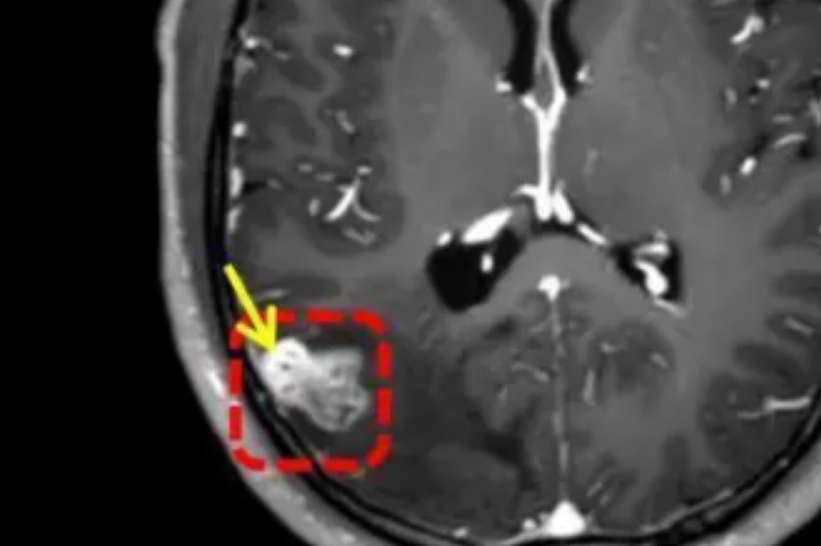

A finales de julio, los síntomas se intensificaron: desmayos, convulsiones, rigidez y espuma en la boca. La resonancia magnética reveló un objeto extraño en su cerebro, confirmando que el parásito había permanecido latente durante años antes de desencadenar complicaciones severas.

Los médicos confirmaron que el hallazgo era un parásito de 18 cm, identificado como Taenia solium, la famosa tenia del cerdo. Para extraerlo, realizaron una craneotomía que resultó exitosa. Tras diez días de observación, Li fue dado de alta en buen estado. Este caso demuestra la gravedad que puede tener ingerir alimentos sin el tratamiento adecuado.